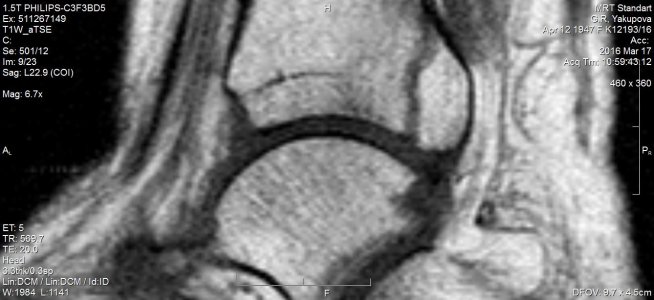

16 марта МРТ заключение: МР- картина консолидирующегося краевого косого перелома дорзальных отделов медиальной лодыжки /без смещения - перелом пилона тип В1 по АО/; остеоартроза голеностопного сустава и стопы: минимального синовита голеностопного сустава. Признаки отека мягких тканей области голеностопного сустава. (фото № 2)